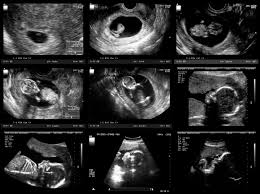

Ab der 4. Das Farbsehen entwickelt sich jetzt recht schnell. Hören kann man die Herztöne in der 78 SSW auch noch nicht man kann das Herz nur im Ultraschall sehen ist aber auch schon wahnsinnig faszinierend.

6 Ssw Kannst Du Schon Das Herz Auf Dem Ultraschall Sehen Hallo Eltern